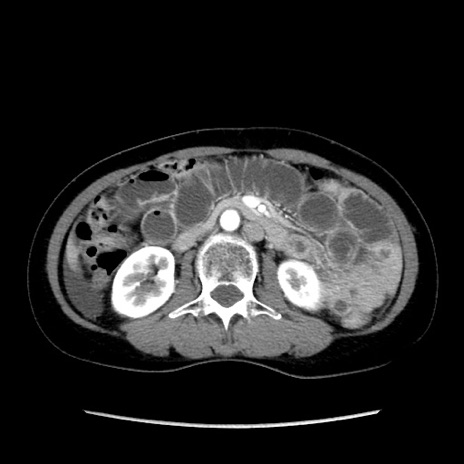

症例32(横断像)

【症例】40歳代 女性

【主訴】上腹部痛、嘔気・嘔吐

【現病歴】約9時間前頃から急に上腹部痛、嘔気、嘔吐が出現。改善しないため救急要請。

【既往歴】子宮頚癌(広汎子宮全摘術、放射線療法)、腸閉塞

【身体所見】腹部:平坦、軟、腸雑音亢進、上腹部を中心に腹部全体に圧痛あり。

【データ】WBC 8400、CRP 0.03